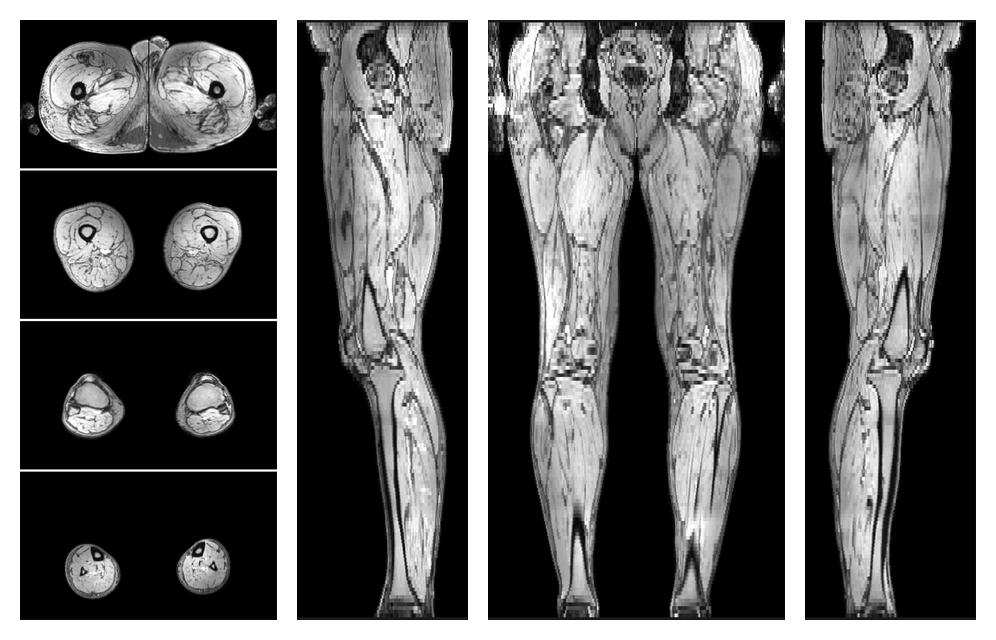

• Automated muscle and bone segmentation.

Overlay of automated muscle segmentation labels on dixon water image.